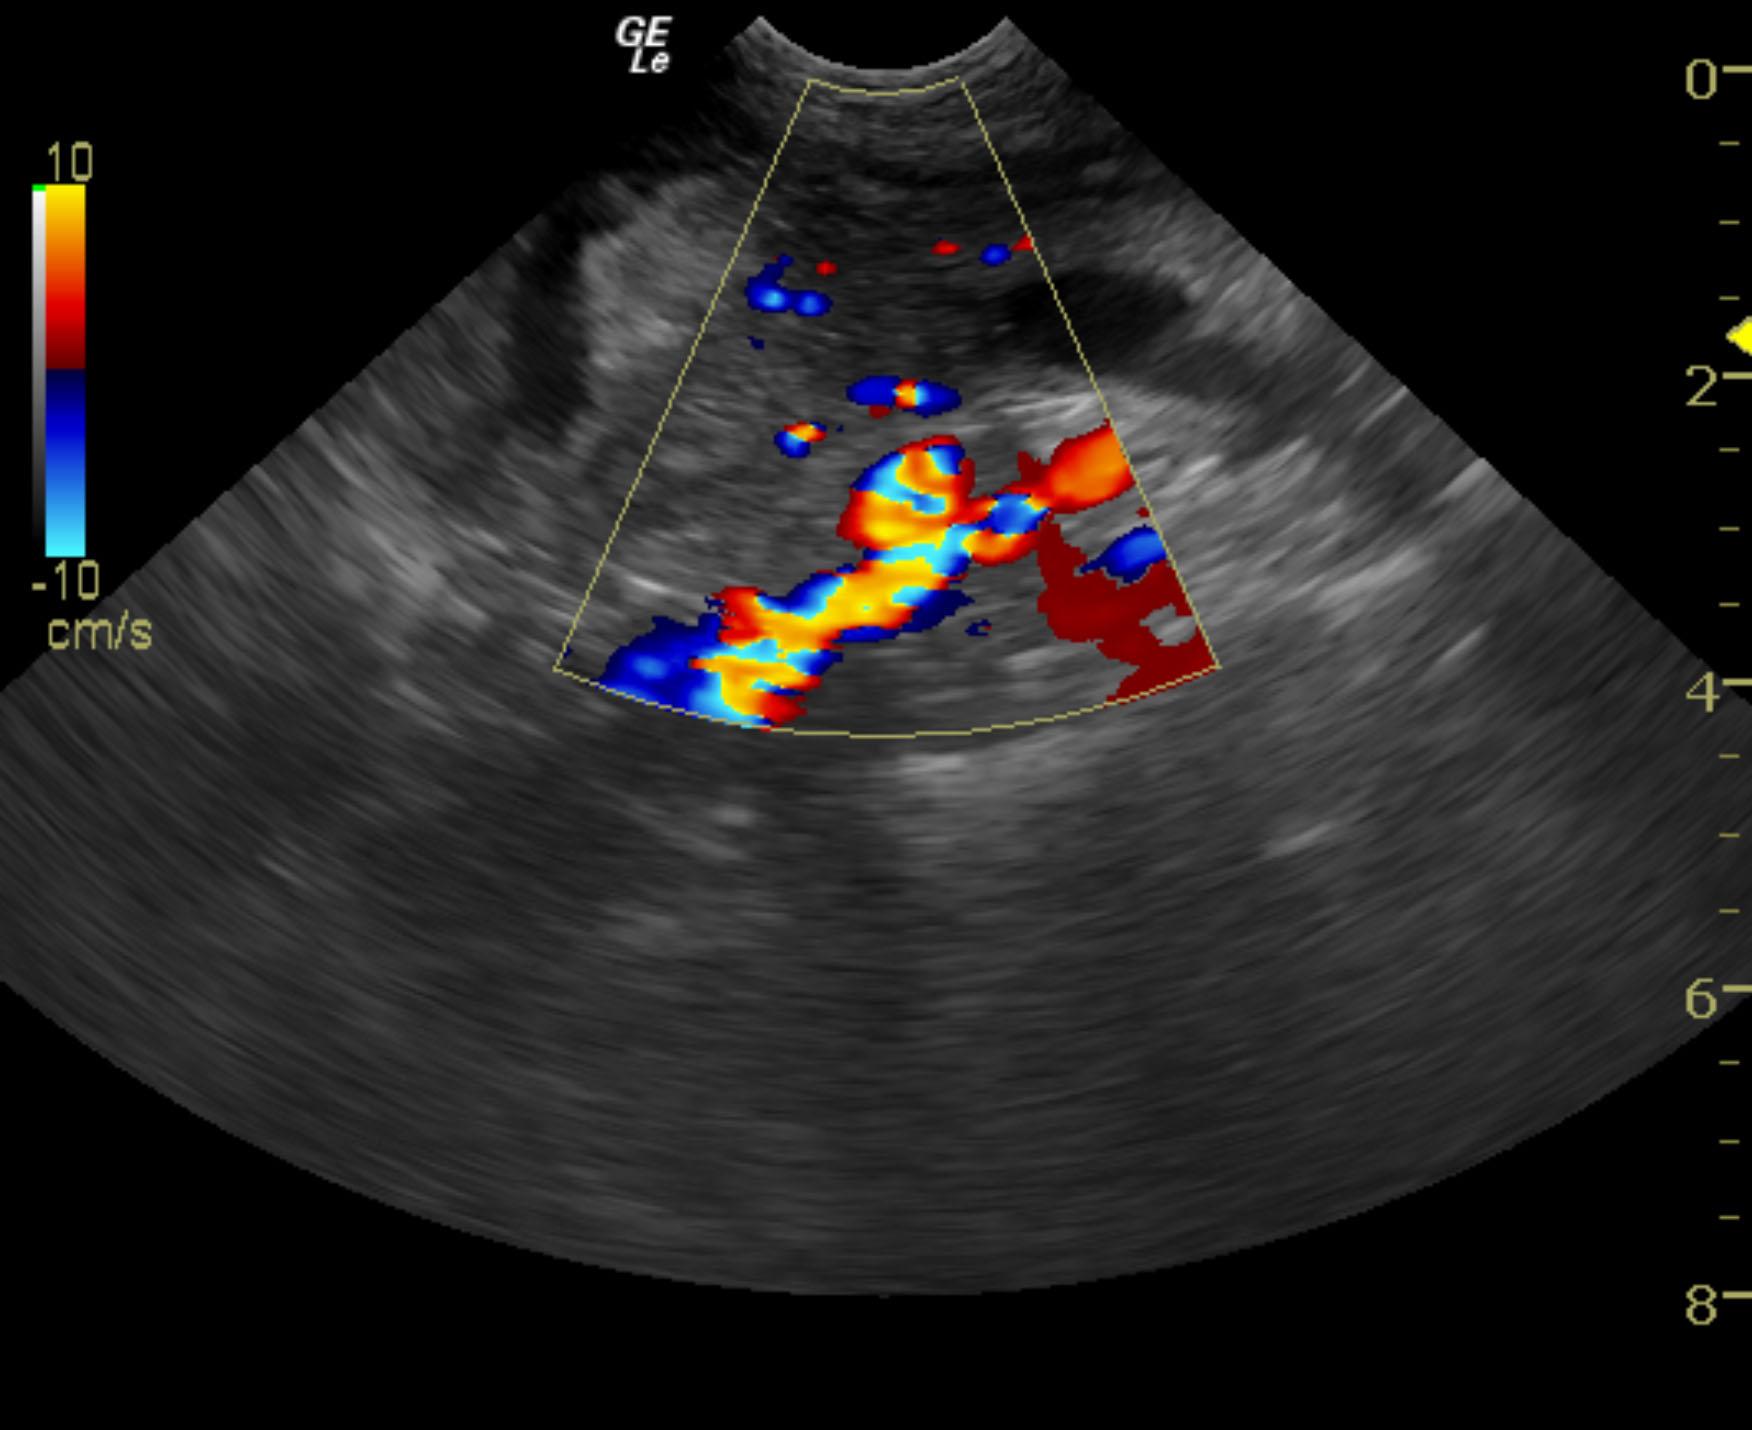

A 10-year-old SF American Eskimo with a history of bladder transitional cell carcinoma that had been stented, chronic renal insufficiency, hydronephrosis, and hydroureter, was presented for evaluation. CBC showed anemia (14%).